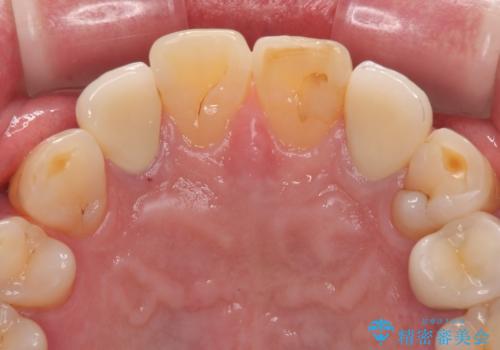

見た目、機能面共に満足していただけました。

右上2番目の歯の違和感もなくなったと喜んでいただけました。

今後もメンテナンスで通ってもらいながら、治療が必要になってきたところは順次行っていく予定です。